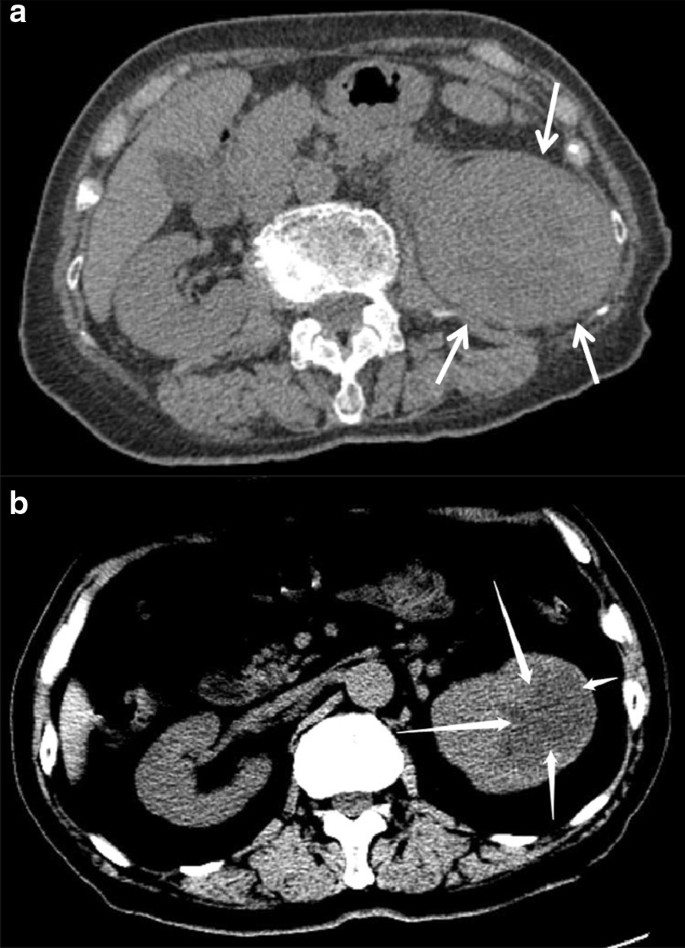

Site and border

The tumor site was varying, with five (38.5%) cases involved the whole kidney, five (38.5%) cases involved the upper pole of the kidney, and three (23.1%) cases involved the lower kidney. Of the 13 patients, six (46.2%) were cortical-medullary involved type and seven (53.8%) were cortex-medullary-pelvis involved type. There were no cases of simple medullary involved type (Table 1). The central part of the tumor was mostly located in the junction zone of the renal cortex and medulla, and the tumors diffused from the cortex and medulla to the inner and outer sides. The medial and renal pelvic structures were unclear. The renal pelvic and renal hilum structures were visibly damaged (Fig. 1a).

a Case 8: coronal enhanced CT image shows a left kidney collecting ductal carcinoma (CDC). The tumor involves the renal cortex, medulla, and renal pelvis. The boundary is unclear (arrows). b Case 12: coronal unenhanced CT image shows a right kidney mass-type CDC. The tumor compresses the surrounding renal cortex and medulla. The boundary is obvious, and is considered the compressed renal cortex (arrows)

The borders of renal CDCs are mostly unclear. In this group of cases, the edge was unclear in 12 (92.3%) lesions, and no obvious signs of capsules were detected. A clear boundary was only observed in one case with a mass type lesion (Table 1). The boundary was assumed to be the compressed renal cortex (Fig. 1b).

Of the 13 cases, 11 (84.6%) were nephritis type and two (15.4%) were mass type (Table 1). There were no significant increases in renal volume in three (23.1%) cases of nephritis type, eight (61.5%) cases of nephritis type had a slight increase in kidney volume, six (46.2%) cases showed a clear outline of the kidney (Fig. 1a), and two (15.4%) cases showed a lobular change in the renal contour. Two cases showed a mass-like enlargement and a marked change in kidney morphology (Fig. 1b).

CT and MRI characteristics

The lesions appeared solid or complex solid and cystic on CT. The unenhanced CT showed high solidity (Fig. 2a), and eight (61.5%) cases had a small cystic component that represented areas of necrosis. The solid areas of the tumor were detected as soft-tissue density that was higher than that of the normal renal parenchyma. The remaining five (38.5%) lesions were complex solid and cystic (Fig. 2b), and all were single cysts. The density was uneven in 12 (92.3%) cases. Multiple sand-like calcifications were observed in one lesion. In this group, seven (53.8%) cases of cortical-medullary-pelvis involved type and two (15.4%) cases of cortex-medullary involved type showed different degrees of caliectasis. Four (30.8%) cases of cortex-medullary involved type did not show caliectasis (Table 1). On MRI, T2WI showed that the affected side was hypointense or isointense to the contralateral renal parenchyma (Fig. 3a, b). The cystic area showed a high signal intensity on T2WI.

a Case 3: axial unenhanced CT image shows a significant increase in the volume of the left kidney CDC. The left medulla is unclear. The lesions are mainly solid components (arrows). b Case 6: axial unenhanced CT image shows mixed density in the left kidney and a clear cystic low-density lesion with a clear border (arrows)